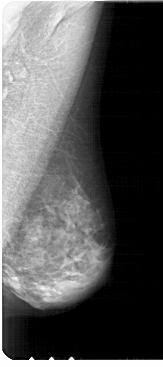

A_1914_1.LEFT_CC

LEFT_CC LINES 4306 PIXELS_PER_LINE 2176 BITS_PER_PIXEL 12 RESOLUTION 43.5 OVERLAY